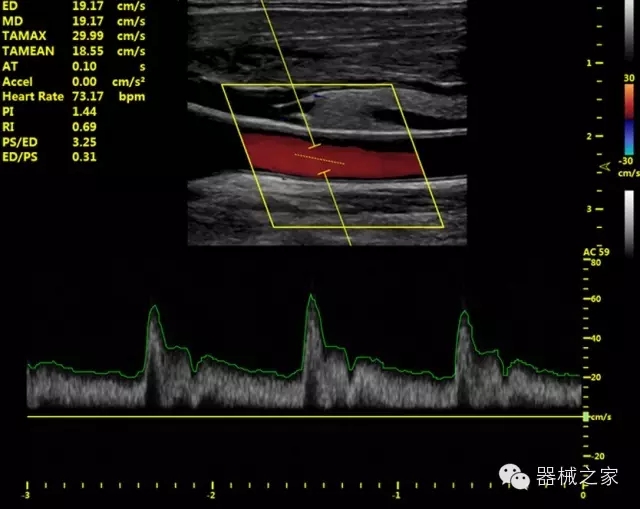

經(jīng)典產(chǎn)品:VINNO 6

臨床圖片賞析

產(chǎn)品特點

·獨有的RF平臺提高微小細節(jié)顯示、圖像對比度和邊界清晰度;

·特有的XCEN探頭,超寬的帶寬,表現(xiàn)更高分辨率和對比度;

·單晶純凈波探頭提供更佳的穿透力和彩色敏感度;

·完整的3D/4D臨床應用,STIC, MCUT 和Auto NT等滿足產(chǎn)科所有應用;

Xcen探頭技術

·獨有的Xcen高頻18MHz探頭,使微小病灶的顯示成為現(xiàn)實,為臨床提供了更廣泛的臨床應用;

·Xcen超寬頻帶探頭技術比常規(guī)探頭頻寬提高了30%,具有更廣泛的臨床應用,更高的頻率讓我們獲得了更好的細微分辨率和對比度的圖像;

·智能感知組織特異性的VTissue技術,結合特有高達22MHzXcen線陣探頭, 以及獨有敏感的RF射頻血流提供了優(yōu)異臨床圖像;

·獨有RF敏感血流使得心臟血流完美呈現(xiàn);